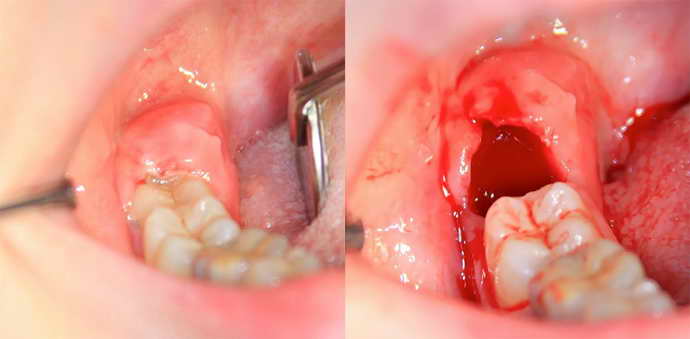

Перед операцией стоматолог делает местную анестезию и осуществляет надрез в десне. После извлечения зуба и его корней на открытую рану накладывают шовный материал.

Операция по удалению зуба мудрости